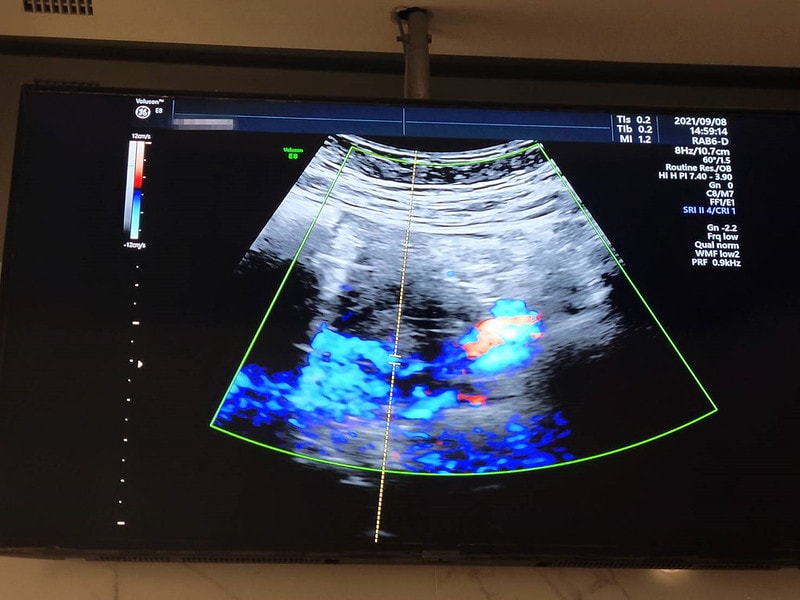

關於孕期出血

(很多孕婦 可能從懷孕到生中間都不會出血)

我自己出血大概是12周的時候遇到的

不知道是不是前一天活動量比較大的關係

檢查內褲發現有鮮血

而且不是淡淡的粉色

就真的是紅色的那種

嚇到馬上直奔婦產科診所

還問醫生說”醫生出血是正常的嗎?”

醫生回了我一句”當然不正常啊”

會開黃體素和安胎藥給你,就是乖乖吃

吃了兩天大概就沒大礙,之後也沒再遇到出血

總之不管是怎樣類型的出血

都不會是正常的

最好還是馬上去看醫生

至於為什麼會出血,有滿多種原因的

醫生是說我有胎盤位置過低的問題

加上和子宮頸中間有條縫隙

如果可能太累或摩擦到就會比較容易出血

就是提醒自己盡量不要提重物

出血的一個月內禁止性行為

還有要注意不要太過疲累

活動量要減少到比懷孕之前少